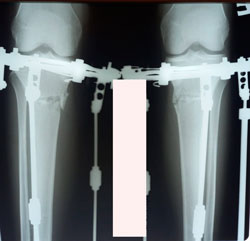

Исходник - 19 лет.

Дата операции - 19.01.2021

image-28-01-21-10-24.jpg

до исправления Ротации с обеих сторон